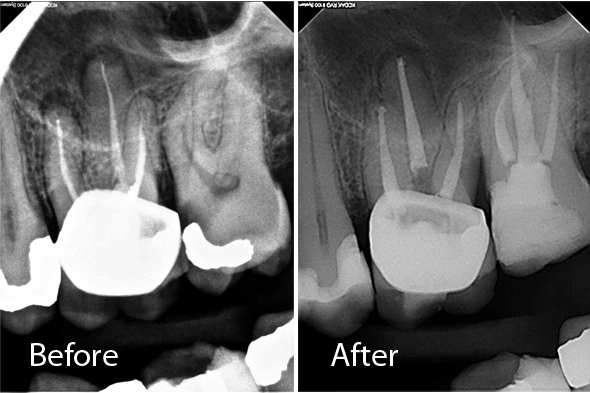

These X-ray images demonstrate the quality and precision of Dr. Portugeys' endodontic procedures. Click any image to view it larger.

Root Canal Premolar – 3 Canals